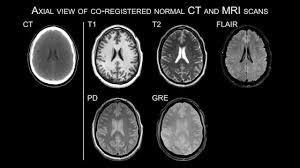

RESSONÂNCIA MAGNÉTICA

Qual o princípio básico?

MAGNETISMO!

LOGO, NÃO PODE SER USADO EM PACIENTES COM MARCAPASSO E NEM PROTESES MAGNÉTICAS!!!

Tipos de ponderações?

T1 (TR e TE baixos)

T2 (TR e TE altos⇒bom para patologias como edema, pois vê água branca)

Outros: FLAIR, DP…

Quais as nomenclaturas?

HIPERINTENSO/HIPERSINAL

ISOINTENSO

HIPOINTENSO

Vantagem da RM?

CORTES ALÉM DO AXIAL (CORONAL, SARGITAL, OBLIQUO)

PODE FAZER SUPRESSÃO DE GORDURA NAS SEQUÊNCIAS